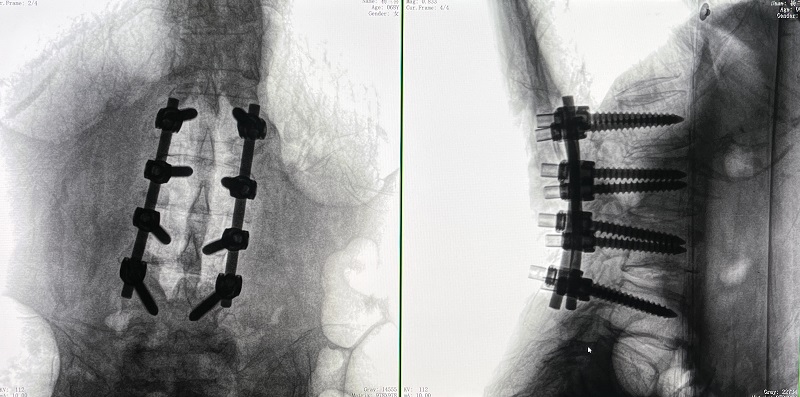

(4)在骨科机器人导航系统辅助下,一次性准确植入8枚椎弓根螺钉。

术后图像